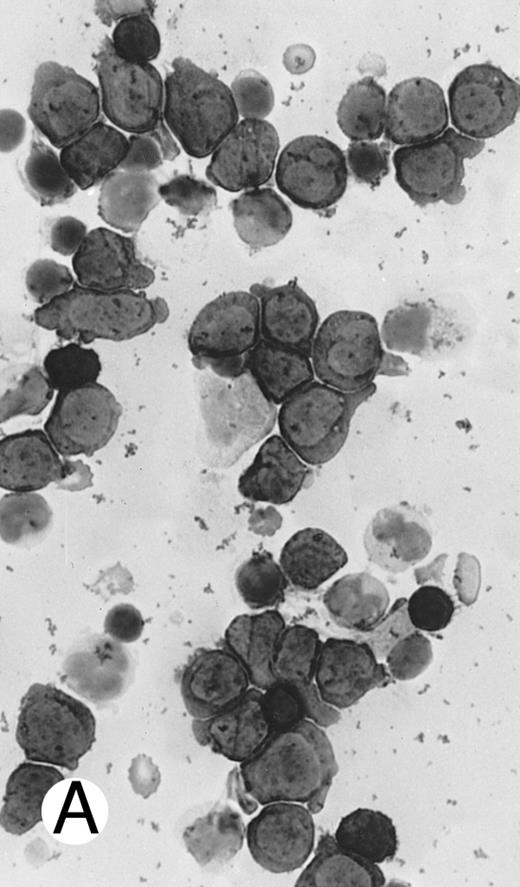

Immunocytochemical staining of aggressive NK cell leukemia/lymphoma (case no. 39), using the labeled avidin-biotin alkaline phosphatase system. The smears were prepared from mononuclear cells separated by density gradient centrifugation using Ficoll-Isopaque. (A) The cells are positive for CD2. (B) There is no reactivity for Leu4/CD3; the strongly stained small lymphocytes serve as internal positive controls. (C) The cells are reactive for CD56 (NKH1).

The immunophenotype as analyzed on fresh/frozen tissues was CD2+ CD3/Leu4− CD4− CD5− CD7− CD8− CD16− CD56+ CD57− (Fig 7). In paraffin sections, the neoplastic cells showed reactivity with the polyclonal CD3ε antibody. In all cases, nuclear labeling for EBER was observed in the majority of neoplastic cells.